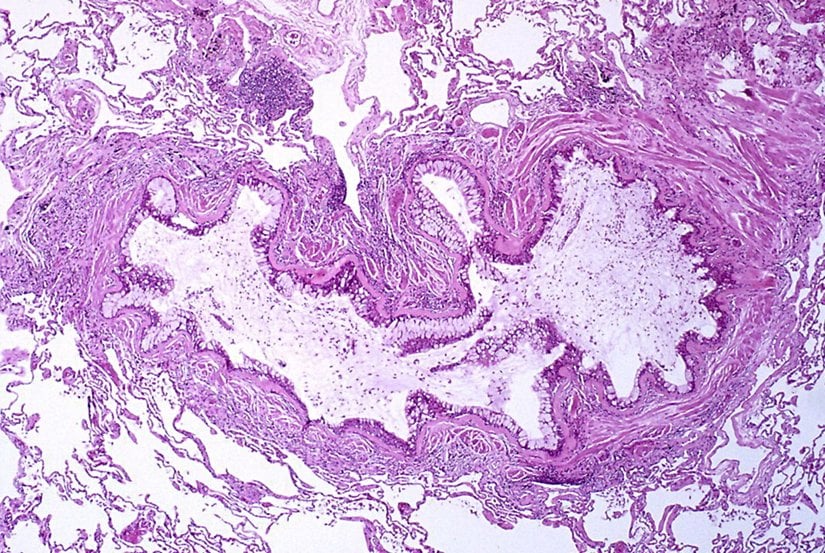

Çeşitli hava yolu tümörlerinin astıma benzer semptomlarla kendini gösterdiği rapor edilmiştir. Bu tümörler, aşağıdaki resimlerde gösterildiği gibi endobronşiyal karsinoid ve mukoepidermoid tümörleri içerir. Bir vakada, sol akciğerinde hiperlüsensi olan 14 yaşındaki bir erkek çocuğunun nihayetinde sol ana bronşta bronşiyal karsinoid olduğu bulundu.[119]

Diğer trakeal lezyonlar arasında bronkosentrik granülomatozis, subglottik stenoz, subglottik ağ, trakeal hamartom, bronkojenik kistler, leiomyoma ve trakeobronkopatia osteoplastika yer alabilir. Tüm bu trakeal lezyon tipleri astıma benzer semptomlarla rapor edilmiştir.